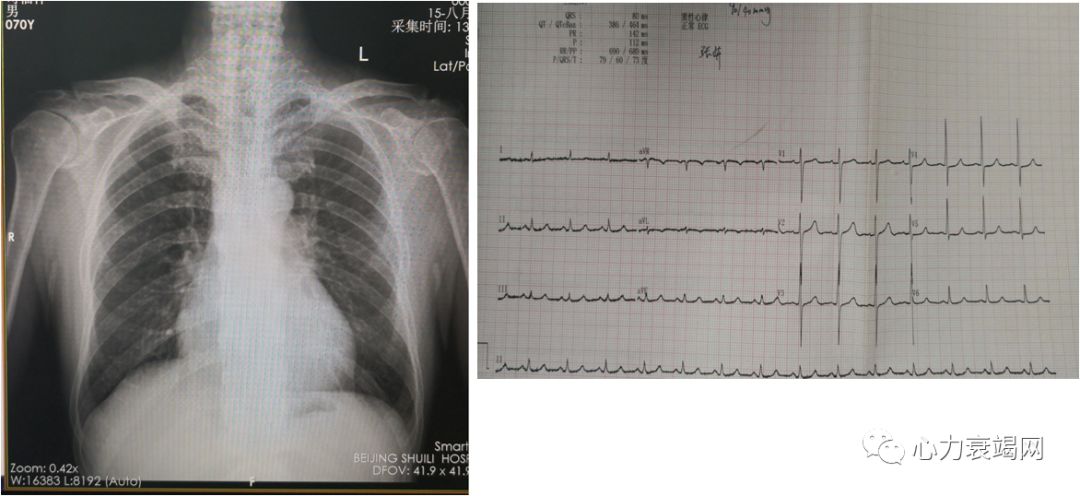

◆ 查体:T36℃,BP120/60mmHg,双肺呼吸音粗,双肺未闻及干湿性罗音,HR90bpm,律齐,主动脉瓣听诊区闻及舒张期叹气样杂音,肝脾未触及,双下肢无水肿,全身皮肤粘膜未见瘀点瘀斑

WBC 9.1×10^9/L HGB 89g/l PLT 265×10^9/L

ALB 34.8g/l Cr 66mmol/l K 3.92mmol/l

ESR 98mm

CRP 97

Po2 167mmHg Pco2mmHg 32 LAC1.3

NT-proBNP4330 pg/ml

心电图